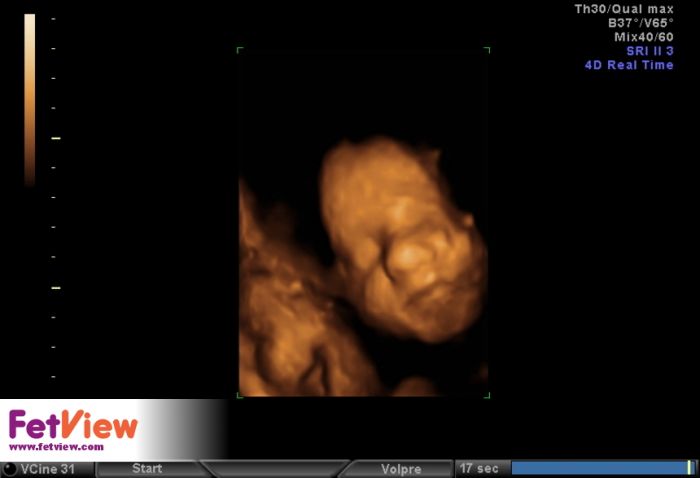

tTak dnešní kontrola ok, 28+4 je to pořád holka a i se nám ukázala, pak na nás vyplázla jazyk :-) váha 1323g a zatím je položená zadečkem dole, ale to se prý ještě změní, má dost času. Takže se mi ulevilo a za odměnu si dneska koupím něco pěkného :-)